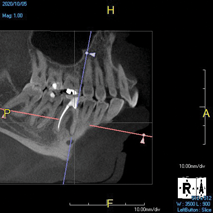

(8.) An original finding of a small lesion on the mesial root of tooth No. 30 was not accompanied by any outward symptoms; therefore, the patient delayed pursuing treatment. When a follow-up CBCT scan was acquired 6 years later, the easy-to-visualize increase in the dimensions of the lesion motivated the patient to elect a treatment plan.

Figure 8

(9.) An original finding of a small lesion on the mesial root of tooth No. 30 was not accompanied by any outward symptoms; therefore, the patient delayed pursuing treatment. When a follow-up CBCT scan was acquired 6 years later, the easy-to-visualize increase in the dimensions of the lesion motivated the patient to elect a treatment plan.

Figure 9